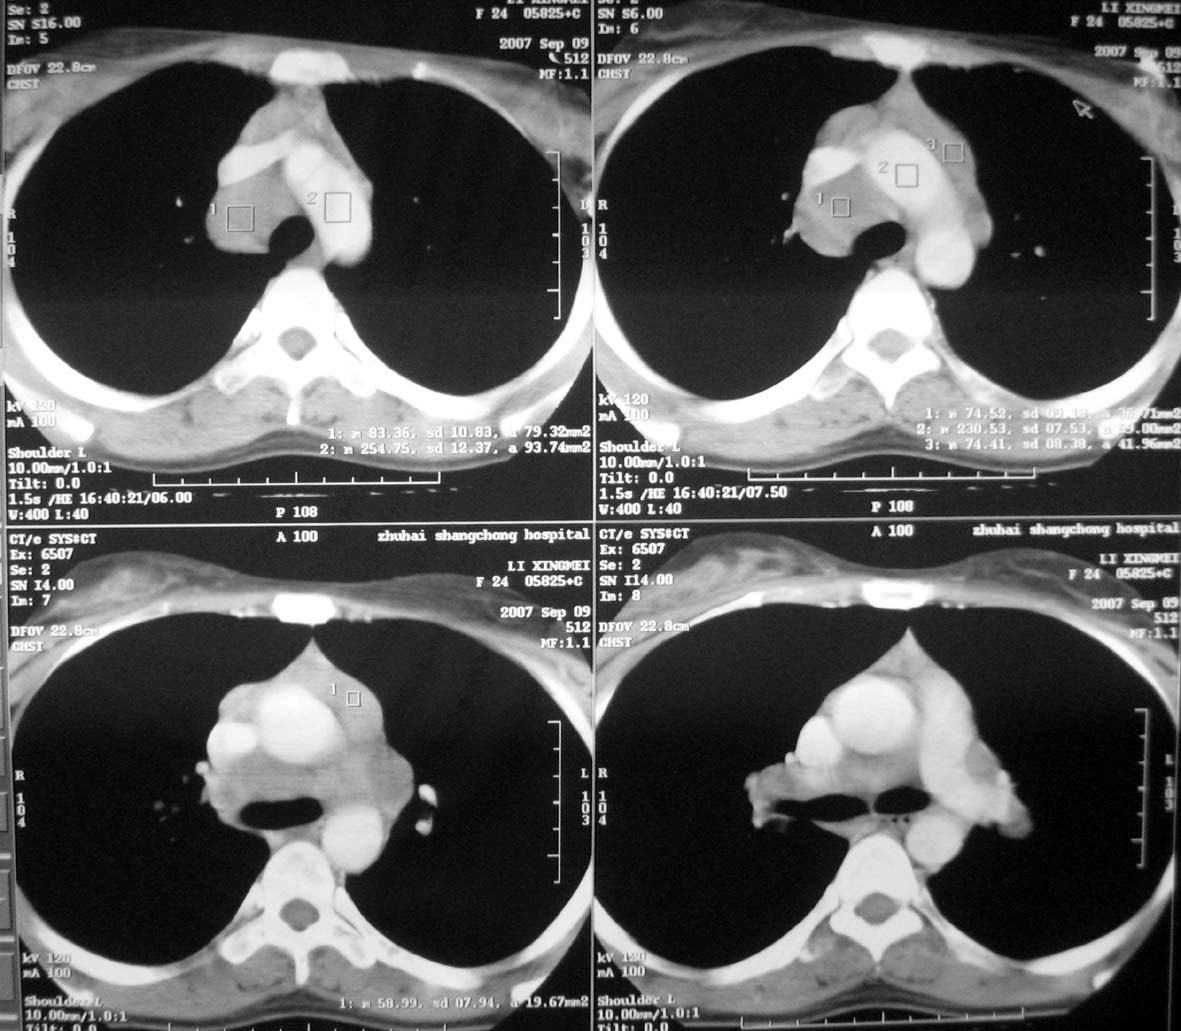

以下是引用qiuleiyu在2007-9-14 19:12:00的发言:[br]纵隔(气管旁组\\隆突下\\主动脉旁组\\血管前组)及肺门淋巴肿大,边界欠清.密度均匀,内无明确钙化.[br]结合临床症状考虑;结节病可能大.[br]鉴别;1,淋巴瘤,可有全身浅表淋巴肿大,肝脾大,发热等.肿大淋巴主要为气管旁组及血管前组及主动脉旁组,肺门肿大不明显.典型者为冰冻纵隔.[br] 2,转移瘤;多见于肺癌,按淋巴链分布肿大,单侧肿大多见,常可见坏死.[br] 3,castlemans;增强后明显血管样强化.内部可有分支状钙化,蜘蛛状瘢痕.周边可有粗大血管.[br] 4,结核;67%有肺部结核灶,肿大淋巴结节,内部可有钙化,增强环状或分格样强化.